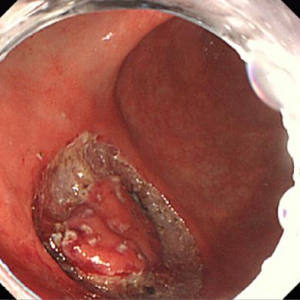

《胃ESDの実際》

食道表在癌、早期胃癌の治療法として当科では積極的にESDを行っています。ESDとは内視鏡的に使用可能な高周波メスを使って、粘膜下層のレベルで病変を剥がし取る手技です。早期の小さな癌に対しては今までも内視鏡治療が行われてきましたが、ESDにより従来の内視鏡治療法(EMR)では切除困難であった大きな病変や、瘢痕を認める病変を一括切除できるようになりました。体を切開することなく組織も温存できるため、患者の身体的負担が少ない低侵襲医療のひとつです。

食道ESDは年間約15例、胃ESDは年間約40例ほど行っております。